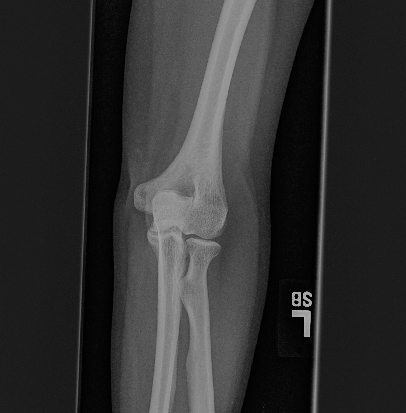

We further compare our method with a classical image enhancement method and a dehazing method for natural images, which uses dark channel prior [5]. The results are shown in Fig. 8 and 9. The classical image enhancement method (histogram equalization) enhances both the soft tissue and bones. And relationship between image intensity and physical X-ray is lost.

Our model is different from the dehazing model. The dehazing method for natural images can not completely remove the soft tissue in X-ray image, as shown by the red arrows in Fig. 8 and 9. In contrast, our method does not have this issue. This is because we estimate a better soft tissue image. Moreover, our bone image has better image contrast, which is theoretically guaranteed as described in previous sections.

Figure 8: (a) original images, (b) image enhancement by histogram equalization, (c) results from dehazing method with dark channel prior and guided filter, and (d) results from our method. The conventional methods can not completely remove the soft tissue (red arrows). Our method does not have this problem (green arrows).

Refer to caption

(a) original

\begin{overpic}[width=199.4681pt]{images/compare/4_he.png} \put(48.0,55.0){\color[rgb]{1,0,0}\vector(1,0){19.0}} \end{overpic}

(b) histogram EQ

\begin{overpic}[width=199.4681pt]{images/compare/4_gf.png} \put(48.0,55.0){\color[rgb]{1,0,0}\vector(1,0){19.0}} \end{overpic}

(c) dehazing

\begin{overpic}[width=199.4681pt]{images/compare/4_U.png} \put(48.0,55.0){\color[rgb]{0,1,0}\vector(1,0){19.0}} \end{overpic}

(d) ours α=1.43𝛼1.43\alpha=1.43

Figure 9: (a) original images, (b) image enhancement by histogram equalization, (c) results from dehazing method with dark channel prior and guided filter, and (d) results from our method. The conventional methods can not completely remove the soft tissue (red arrows). Our method does not have this problem (green arrows).